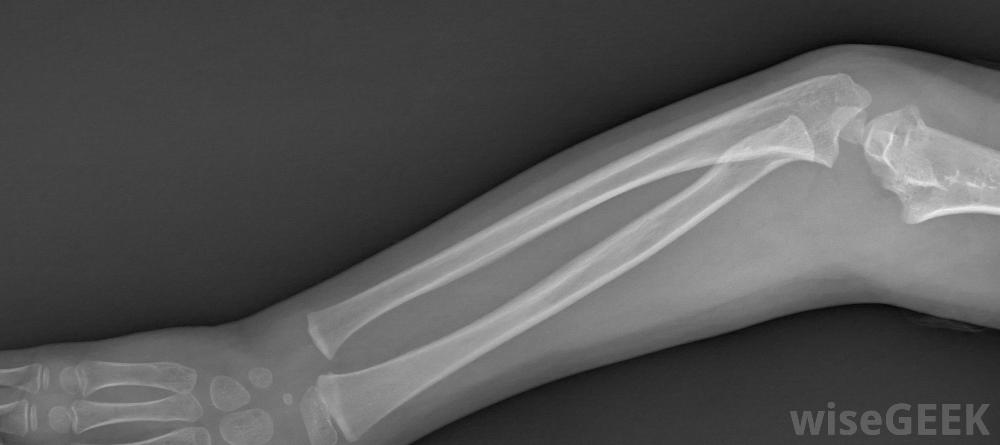

物理疗法是治疗臂丛损伤的两种主要方法之一为了确定对病人的适当治疗,医生通常会首先进行一系列的检查。如果伤情发生后立即对患者进行评估,以获得最佳的臂丛治疗效果,通常情况下,检查首先要对受伤的手臂进行身体检查和x光检查。为了帮助诊断,医生可以要求进行肌电图(EGM)测试,这包括将一个小电极针插入皮肤来测试肌肉及其神经。神经科医生通常会检查结果并确定神经损伤的严重程度。

臂丛神经治疗通常从对受伤手臂进行x光检查开始,大多数人选择物理疗法作为臂丛神经治疗的形式物理治疗的时间长短通常取决于损伤的严重程度和患者的进展情况。臂丛神经的锻炼可以包括各种手臂伸展、手和手腕的锻炼,以及不同范围的运动练习。这些运动可以防止手臂僵硬,有助于增强手臂,一旦病人接受了专业理疗师的训练,他们通常会被鼓励在家里做同样的运动。在更严重的情况下,手术是臂丛神经治疗的主要方式患者在接受物理治疗后无法恢复,通常在受伤后的三到六个月内进行手术。有几种手术可以修复或替换受损的神经,可以通过神经移植和神经转移来完成。手术后,许多人在物理治疗后的两到六个月内就可以恢复手臂的完全活动。臂丛神经损伤的人不应该放弃充分利用受伤的手臂。为了完全康复,通常是这样最好听从医生的指示。通常建议患者认真对待物理治疗练习或手术,不要过度劳累他们的损伤。